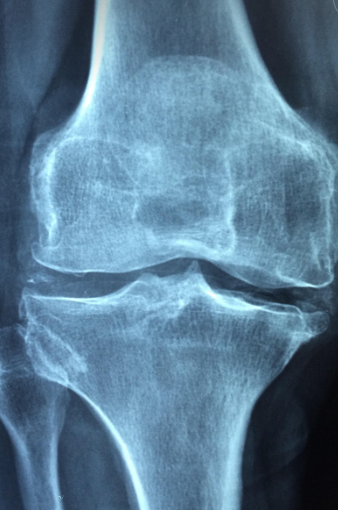

무릎 급성골괴사는 무릎뼈 내부로 가는 혈류가 갑작스럽게 차단되면서 뼈조직이 괴사 되는 질환으로, 주로 중장년층과 골다공증 환자에게 발생합니다. 심할 경우 관절 붕괴로 이어져 일상생활에 큰 불편을 초래하기 때문에 조기 진단과 정확한 치료가 중요합니다. 무릎 골괴사에 대한 개요와 함께 수술적 치료와 비수술 치료를 비교하며, 최근 각광받고 있는 고주파 치료, 줄기세포 치료, 인공관절 치환술의 원리와 적용 사례까지 자세히 안내합니다.

무릎 골괴사가 일정 수준 이상으로 진행되면, 뼈 내부가 무너지고 관절 표면까지 손상되면서 더 이상 비수술적 치료로 회복이 어려워집니다. 이 경우 대표적인 수술 방법은 인공관절 치환술과 관절정렬교정술(절골술)입니다. 인공관절 수술은 괴사 된 무릎뼈와 연골을 제거하고 금속 및 고분자 재질로 된 인공 부품을 삽입하는 방법입니다. 이 수술은 주로 3~4단계 말기 환자에게 시행되며, 통증 완화와 보행 기능 회복에 매우 효과적입니다. 특히 최근에는 로봇 수술과 3D 프린팅 기술이 도입되어 수술 정확도가 높아지고 수술 후 회복 시간도 단축되고 있습니다. 또 다른 수술법인 절골술은 무릎뼈의 하중이 가해지는 방향을 바꿔주는 방식으로, 괴사 된 부위를 보호하면서 통증을 줄여줍니다. 젊은 층이나 활동성이 높은 환자에게 적합하지만, 회복 기간이 길고 정확한 정렬이 필수입니다. 수술은 단기적으로 매우 효과적이지만, 감염 위험이나 인공관절의 수명(보통 15~20년)에 따라 재수술이 필요한 경우도 있어 의료진과의 충분한 상담이 필요합니다.

무릎골괴사가 초기 단계(1~2기)에 머물러 있다면, 수술 없이 회복을 도모할 수 있는 다양한 비수술 치료법이 존재합니다. 대표적인 방법은 고주파 열치료(RFA)와 체외충격파 치료(ESWT), 약물치료, 운동 및 체중 조절 등이 있습니다. 고주파 치료(RFA)는 미세한 탐침을 무릎 뼈에 삽입한 뒤 고주파를 이용해 괴사 된 부위의 염증을 줄이고, 통증 신경을 차단하는 방식입니다. 시술 시간이 짧고 회복이 빠르며, 비교적 부담이 적은 비수술 대안으로 주목받고 있습니다. 또한, 체외충격파 치료는 뼈조직 재생을 유도하며, 혈류를 자극하여 괴사 진행을 늦추는 역할을 합니다. 여러 회기 동안 지속적으로 받아야 효과가 나타나며, 통증이 비교적 적은 것이 장점입니다. 약물치료로는 혈류 개선제, 항응고제, 칼슘 및 비타민D 보충제 등이 사용되며, 골밀도를 향상하고 염증을 줄이는데 도움을 줍니다. 이 외에도 무릎에 부담을 줄이는 생활 습관 개선과 체중 감량 역시 비수술 치료의 핵심 요소입니다. 단, 이러한 치료법은 진행된 괴사에는 효과가 제한적이므로 반드시 정기적인 MRI 검사를 통해 상태를 확인하면서 병의 진행을 모니터링해야 합니다.

무릎 급성골괴사는 치료 시기에 따라 수술적 접근과 비수술적 치료가 갈리며, 초기에는 고주파 치료나 줄기세포 치료 같은 새로운 기술이 효과를 보입니다. 말기에는 인공관절 치환술이 필요한 경우도 있으므로 조기 진단이 가장 중요합니다. 정확한 진단과 맞춤형 치료 계획을 통해 무릎 건강을 지키고 삶의 질을 높여보시기 바랍니다.